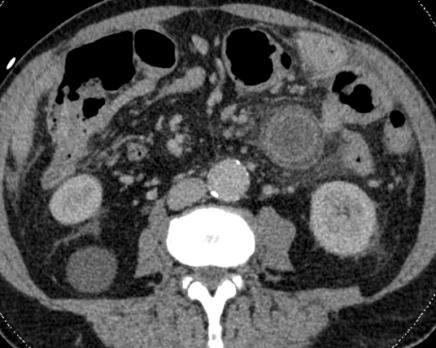

Een 60-jarige patiënte met pijn in de rug en bil onderging een CT-scan van de buik. De voorgeschiedenis vermeldde twee jaar

Een aneurysma van de arteria lienalis is een zeldzame diagnose, zeker bij een jonge, gezonde vrouw. Dit type aneurysma is geassocieerd met onder andere atherosclerose, andere vaatwandziekten zoals bindweefselziekten, (portale) hypertensie en verhoogde viscerale flow. Het exacte ontstaansmechanisme is nog niet bekend. Niet-geruptureerde aneurysmata zijn bijna altijd asymptomatisch. In minder dan 5% van de gevallen zijn er aspecifieke symptomen. Het is dus een diagnose die vaak bij toeval wordt gesteld. Uitstel van de diagnose kan leiden tot het ruptureren van het aneurysma en dit gaat samen met een hoge morbiditeit en mortaliteit. CT-angiografie is het diagnosticum van keuze voor het aantonen van dit aneurysma. Asymptomatische aneurysmata worden nagenoeg altijd behandeld, gezien het risico op ruptuur. Alleen bij ernstige comorbiditeiten van de patiënt is follow-up van het aneurysma te overwegen. Zowel een endovasculaire als een chirurgische behandeling is mogelijk.